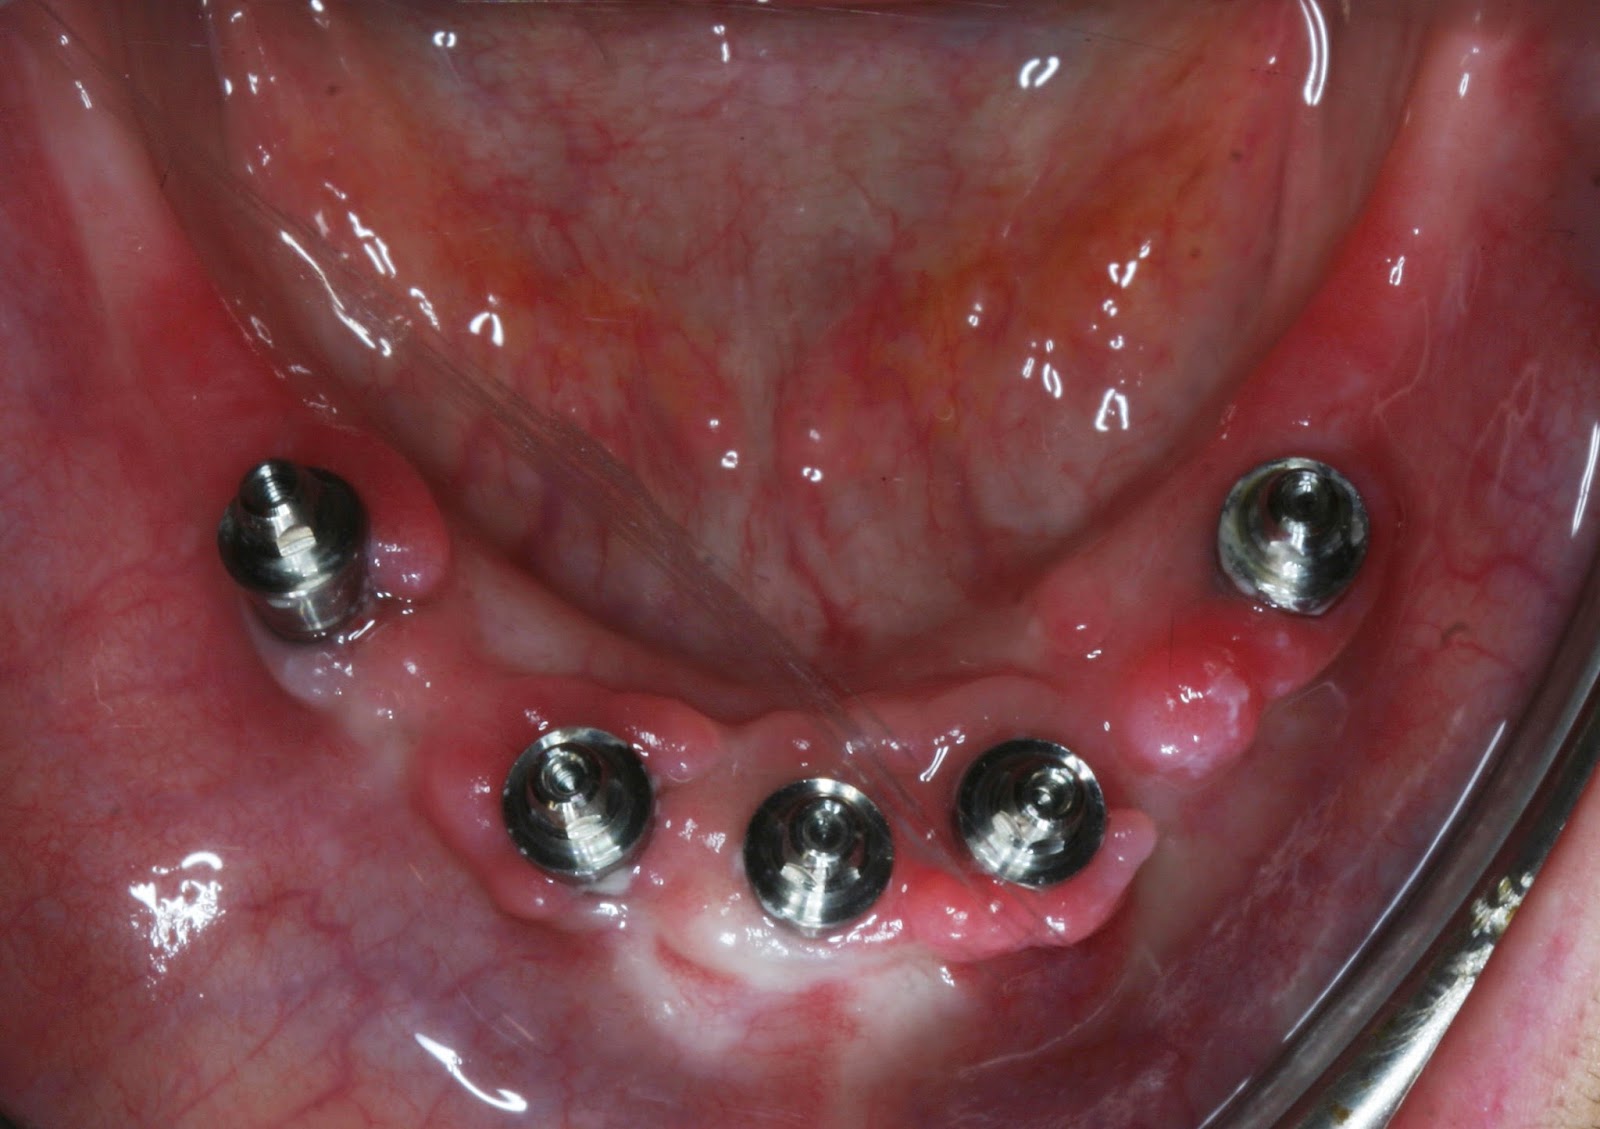

nos lembrávamos. Eu, São, fiz de cobaia e avancei primeiro. Aqui está uma foto dos meus implantes de baixo)

Tudo correu bem, e

apesar de algum inchaço normal e uma ou outra nódoa negra, fiquei como nova. O

Dr. Ricardo colocou-me lá os parafusos todos necessários e não posso dizer que

tenha sofrido muito… é sempre desconfortável, claro, mas pensei sinceramente

que fosse pior. Já comigo, Aida, a minha cirurgia foi mais difícil, porque

tinha menos osso que a São. Tive que ter mais alguns cuidados, mas felizmente

consegui manter cá todos os implantes com sucesso! Com a cirurgia ganhámos um